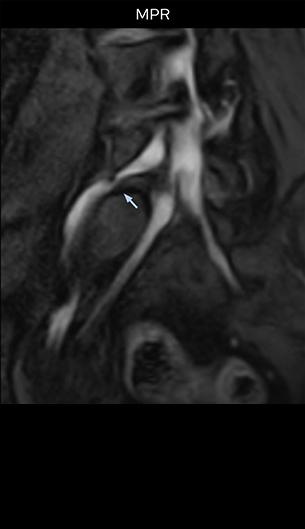

“For example, in sagittal images, when the presence of fat is observed in the intervertebral foramen, it suggests that there is a margin around the nerve. Similarly, the absence of fat indicates that the nerve is being compressed. So, we used to deduce nerve compression indirectly. With NerveVIEW, however, we can observe the condition of the nerves directly, regardless of the presence or absence of fat. We always prefer such direct observation of anatomy over having to make an inference about it.”

“Although symptoms of typical disc herniation and atypical hernia are very similar, the actual site of herniation is different. It is therefore important to characterize the nerve’s condition both inside and outside of the intervertebral foramina. “Conversely, if we see no abnormality in NerveVIEW, we can assume at least that there is no severe condition that requires surgery. Like this, it can help us avoid unnecessary surgery. NerveVIEW can have a tremendous impact in this way.”

“The intra-luminal signal of veins, especially around the intervertebral space, can be suppressed well with NerveVIEW. As a result, we can easily observe the detailed nerve structure around the posterior ganglion,” he says. “This is why we use 3D NerveVIEW for intraforaminal stenosis and extraforaminal stenosis/herniation (lateral disc herniation). On the other hand, if herniation is suspected to exist inside the dorsal root ganglion (DRG), balanced TFE or ProSet-FFE is applied. NerveVIEW is not suitable for evaluating the median type of herniation.” The SE-EPI DWI-based method for MR neurography works well for large FOV exams like whole-body MRI, but focal examination of nerves is often limited by the attainable spatial resolution (both inplane and slice direction) and geometric distortion. “3D NerveVIEW achieves higher in-plane resolution – close to our other routine spine sequences – and the source images can be used instead of adding a fat-suppressed T2-weighted sequence,” Tanji says.

“NerveVIEW can clearly show nerve courses and presence of nerve compression. However, when multiple abnormalities are seen, it can still be hard to determine which nerve is causing the symptoms,” says Dr. Yabuki. “In our experience so far, we see abnormal findings on NerveVIEW in about 70% of elderly patients. As the pain is usually caused by only one nerve, we thus need to find the exact corresponding nerve.” “With a nerve root block, the patient's pain is improved by infiltration of local anesthesia directly around the nerve root considered to be responsible. Knowing such nerve root block findings prior to image interpretation, helps to easily recognize abnormal findings on NerveVIEW as well. In other words, without a priori knowledge, based on symptoms and/or nerve root block findings, we must be aware of the possibility of overdiagnosis.”